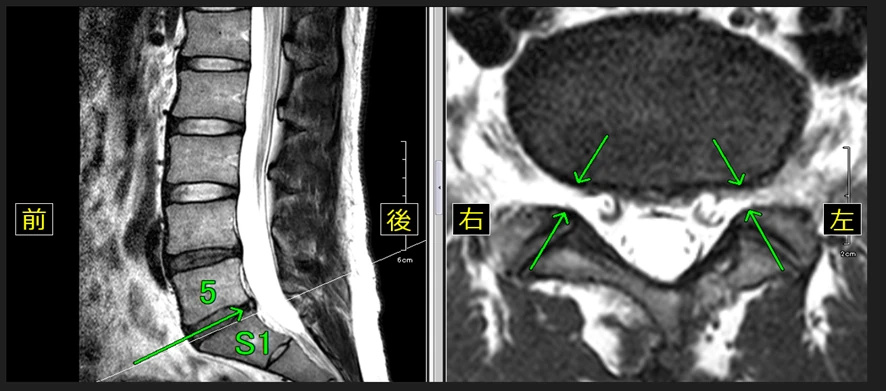

【14級レベルの腰椎のMRI画像】

※腰椎椎間板の軽度の膨隆が認められます